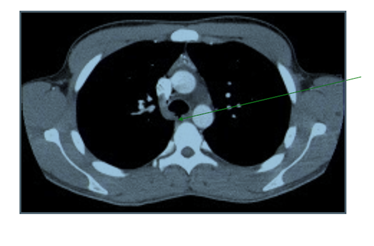

While still in the emergency department, he continued to have hemoptysis and developed palpable surgical emphysema at the root of the neck which raised suspicion of an ongoing air-leak from a TBI. A CT scan of the thorax was done and it showed a posterior tracheal tear 1.5cm above the carina as shown in Figure 2 and bilateral lung contusions, shown in Figure 3. His dyspnea and surgical emphysema continued to worsen, so he was intubated and immediately transferred to the nearest cardiothoracic centre.

Figure 3 CT Thorax transverse view showing lung contusions.